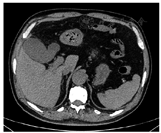

经多科会诊讨论并与患者家属商议后,给予患者胃肠减压、液体复苏、血液透析、皮下注射低分子量肝素钙(4 100 U/12 h)、静脉滴注泮托拉唑钠(80 mg/12 h)、美罗培南(500 mg/8 h)及莫西沙星(400 mg/次,1次/d)等保守治疗。经过5 d治疗,患者病情逐渐好转,腹痛消失。复查C反应蛋白正常,大便潜血阴性;复查腹部CT提示门静脉及分支内气体完全消失(图2)。患者治疗好转后出院,目前仍于本院透析室规律血液透析治疗。

注:肝门静脉及其分支内所有气体完全消失